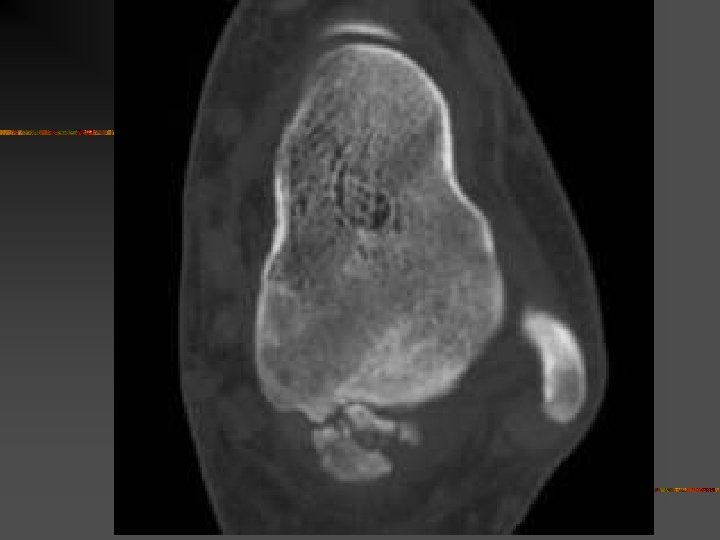

Kyste anévrysmal calcanéen